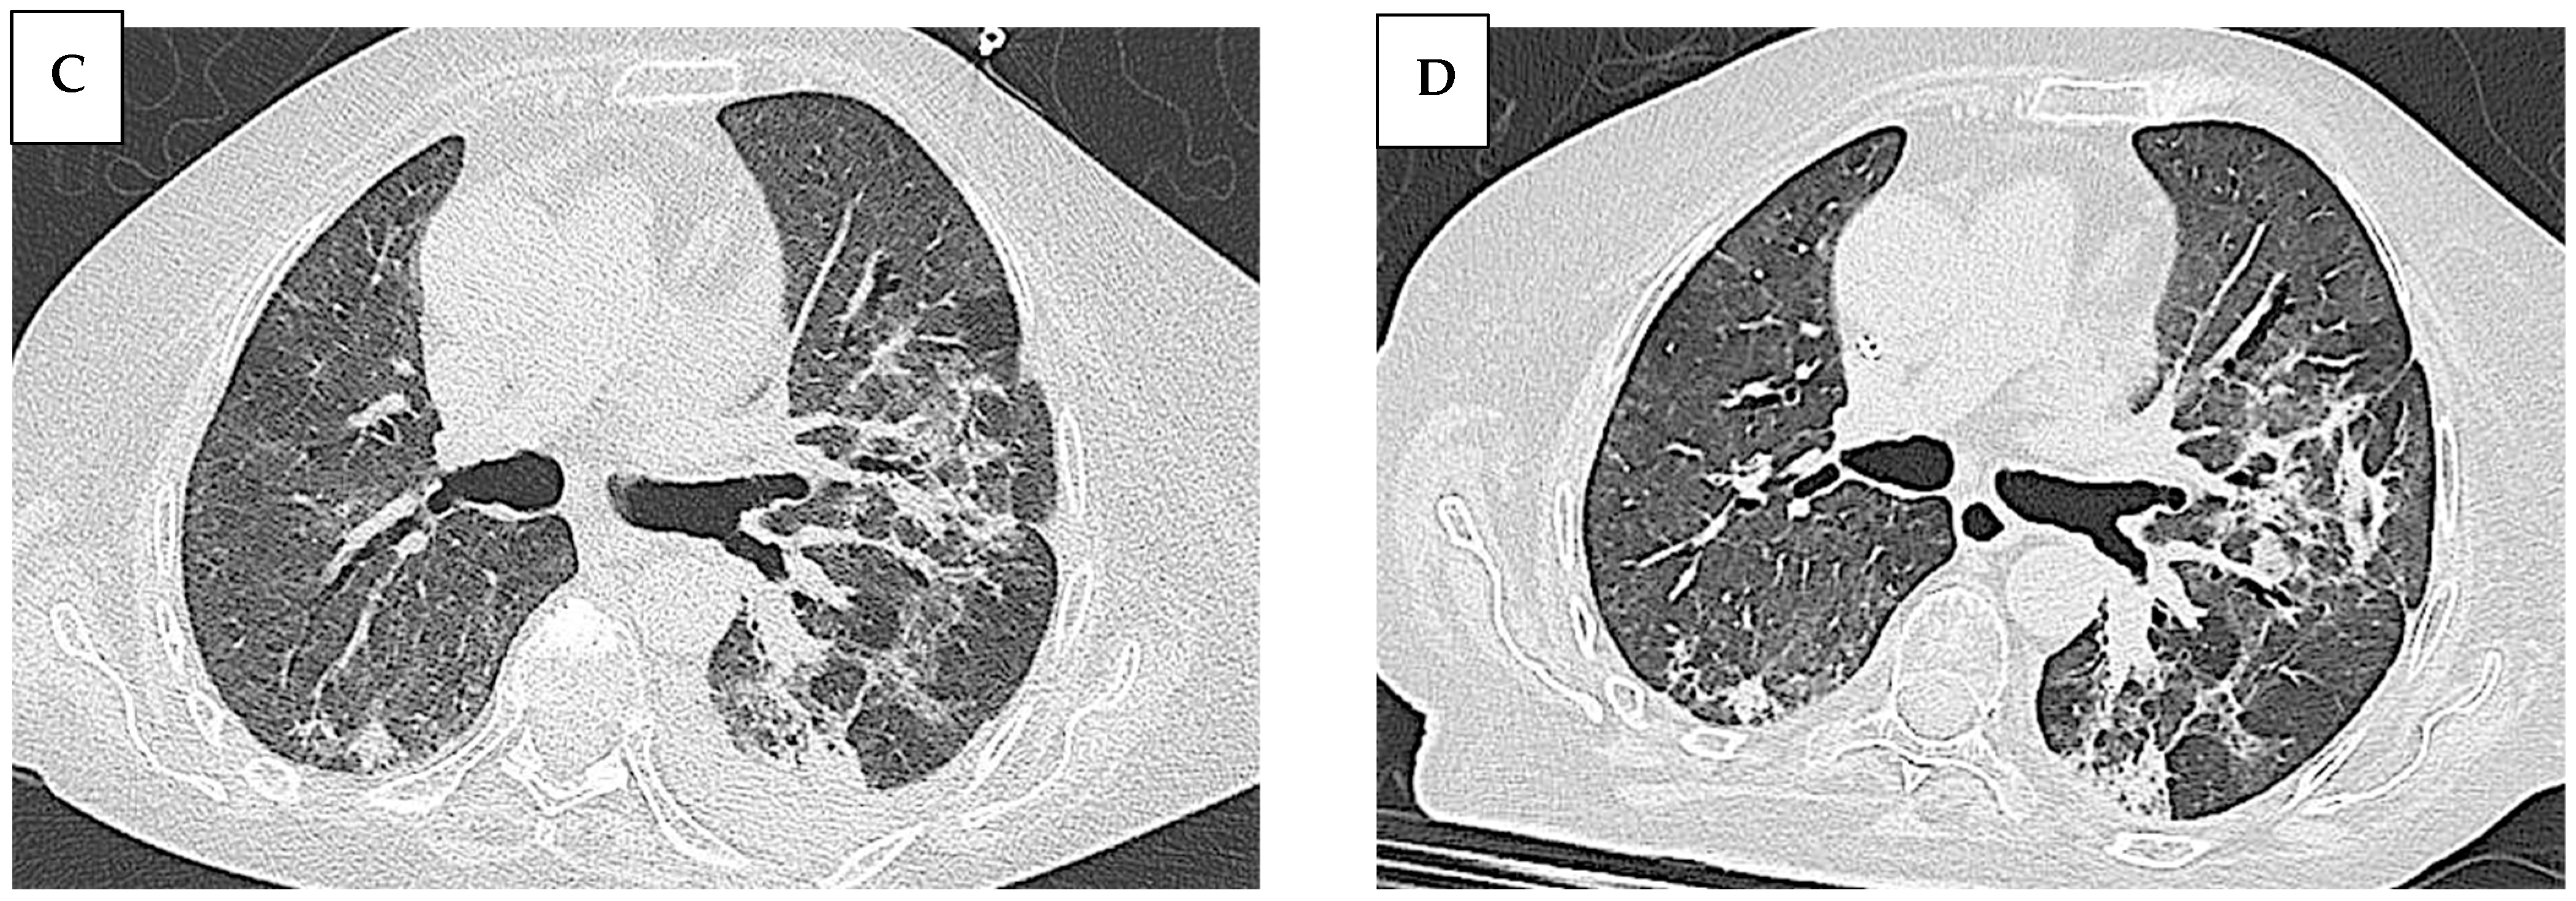

| Our patient | 68 | female | - ASyS - SD | - ANA (anti-Golgi pattern 1:1280) - anti Ro/SSA - anti PL-7 | - Raynaud Phenomenon: no - Arthralgia: no - Muscle weakness: no - Muscle enzyme elevation: no - Dyspnea: yes | NSIP | - Methylprednisolone bolus therapy (1 g/day for 3 days) - IVIG therapy (400 mg/Kg per day for 5 days) - Mycophenolate mofetil (3 g/day) - Nintedanib (300 mg/day) | The patient passed away 3 months after the initiation of immunosuppressive therapy |